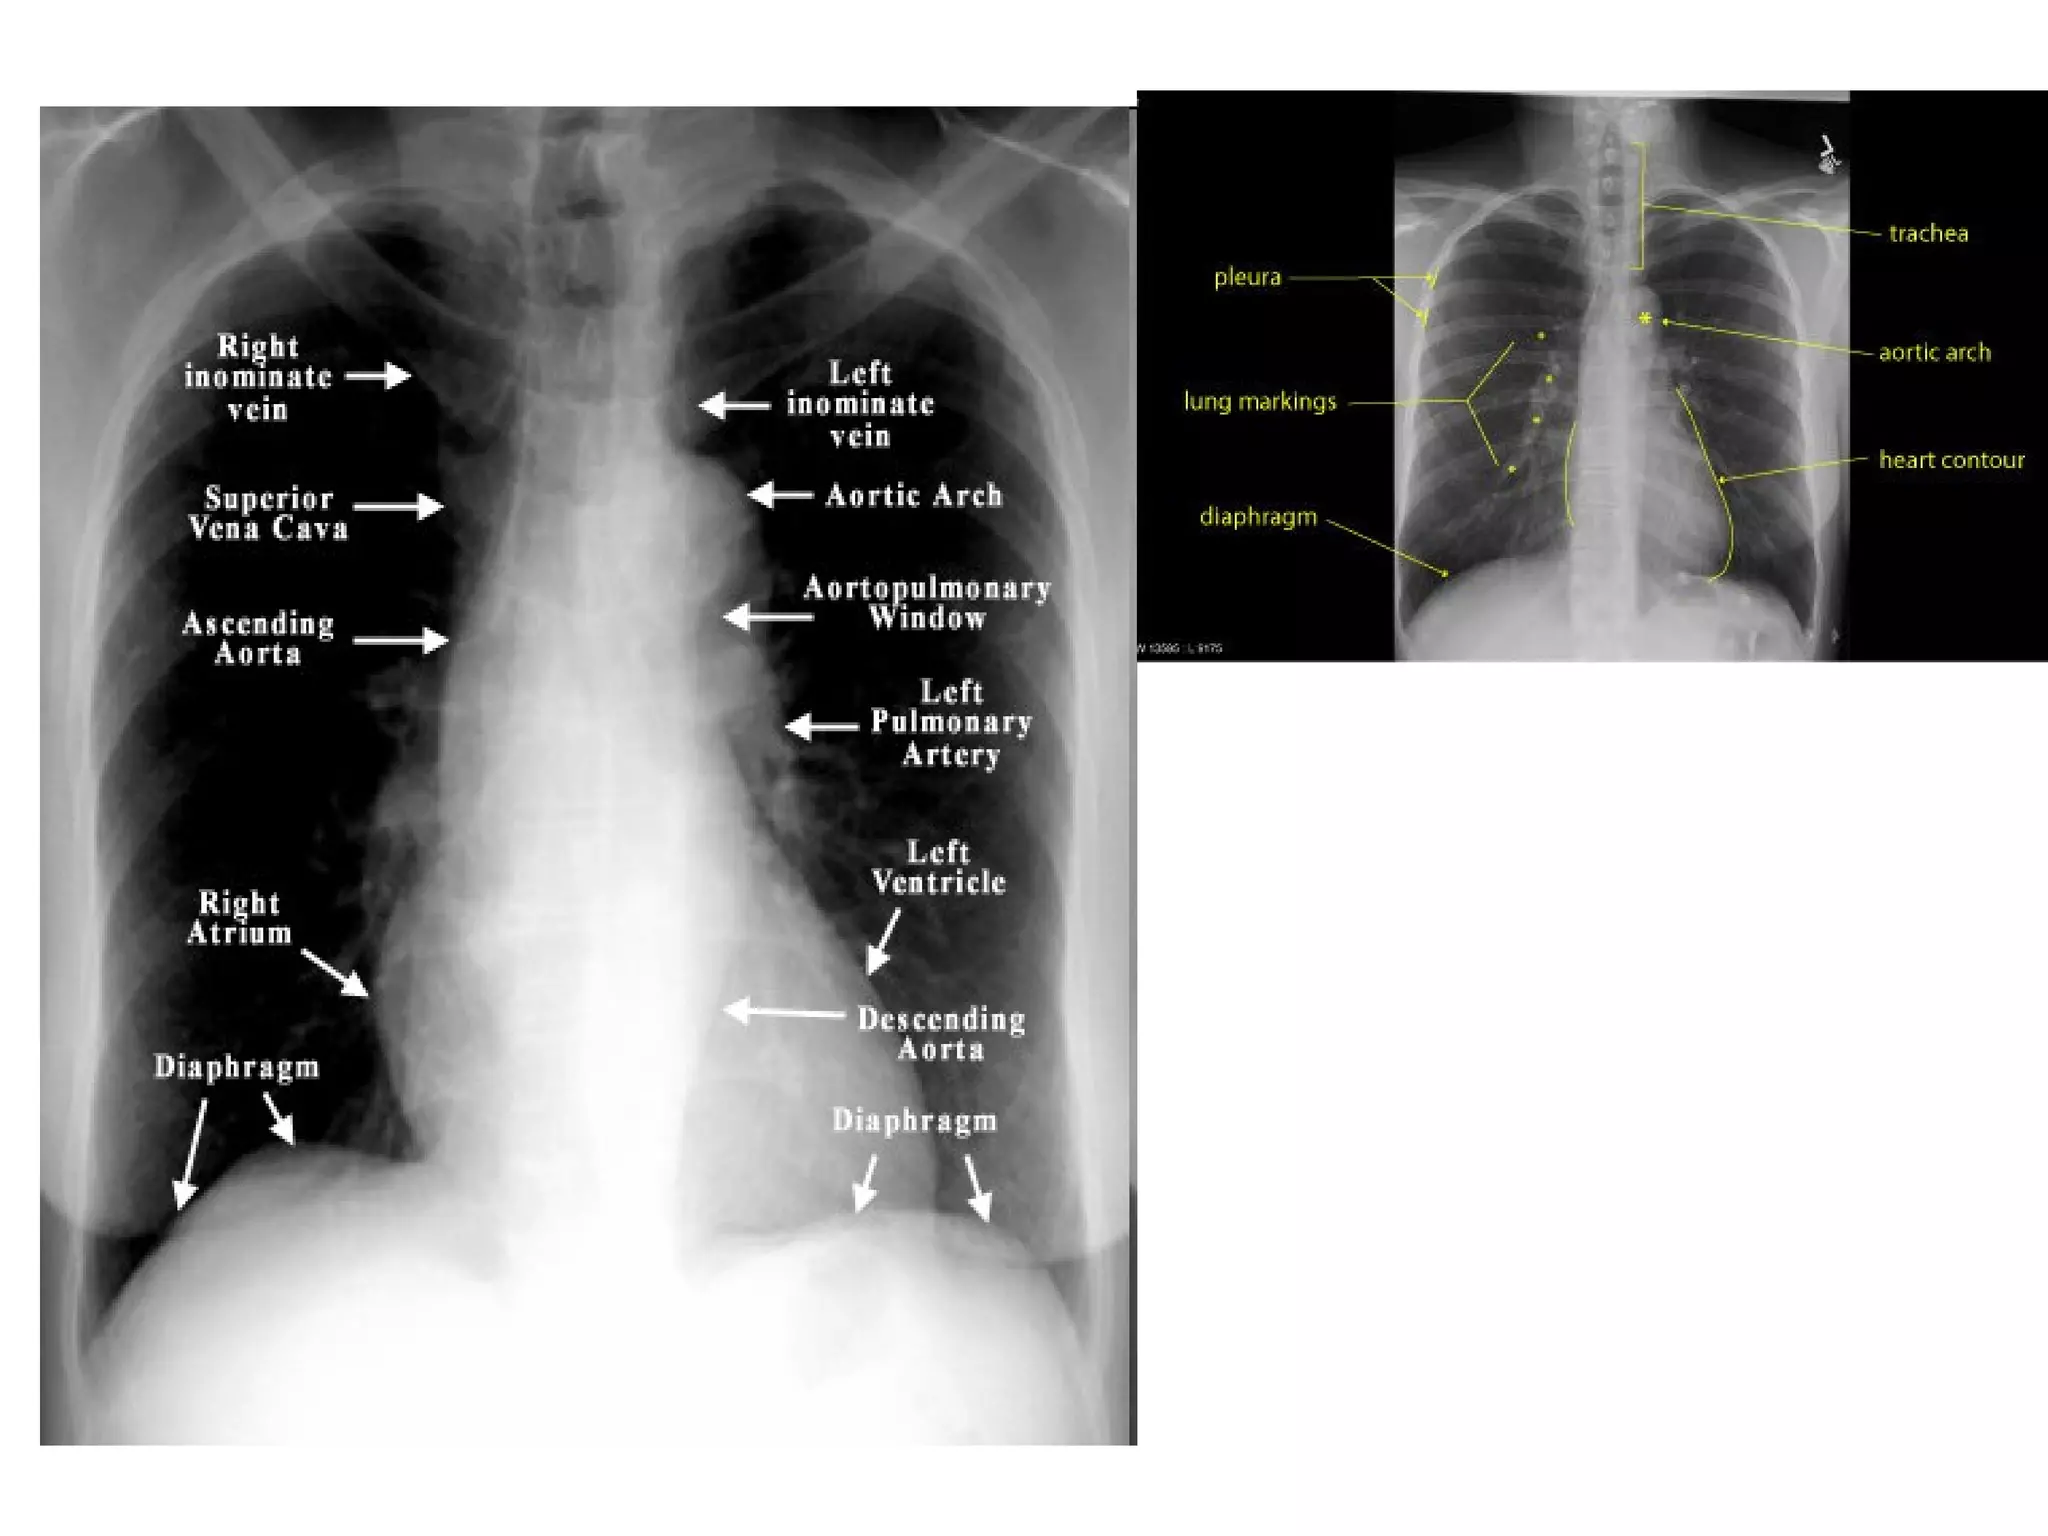

The mediastinum and heart

The central dense shadow seen on PA CXR

comprises the mediastinum, heart, spine and

sternum

The cardiac shadow lies to the left of the midline

and 1/3 to the right although it is quite variable

The transverse cardiac diameter normal for female

< 14.5 cm and for males < 15.5 cm.

The normal cardiothoracic ratio is < 50% on PA

film and < 60% in AP film.

An increase in excess of 1.5 cm in the transverse

diameter on comparable serial films is

significant.

All borders of the heart and mediastinum

should be clearly defined

Superior

Vessels

Vena

Cava          Aortic Arch

Ascending

Aorta        Pulmonary Artery

Right          Left Atrium

Atrium

Inferior        Left Ventricle

Cava

The mediastinum andheart The central dense shadow seen on PA CXR comprises the mediastinum, heart, spine and sternum The cardiac shadow lies to the left of the midline and 1/3 to the right although it is quite variable The transverse cardiac diameter normal for female < 14.5 cm and for males < 15.5 cm. The normal cardiothoracic ratio is < 50% on PA film and < 60% in AP film. An increase in excess of 1.5 cm in the transverse diameter on comparable serial films is significant.

Superior Vessels Vena Cava Aortic Arch Ascending Aorta Pulmonary Artery Right Left Atrium Atrium Inferior Left Ventricle Vena Cava